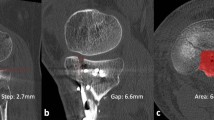

In cases of severe calf trauma, such as tibial diaphyseal fractures, the anterior compartment is most frequently affected [8], so we measured and recorded the ICP in the anterior compartment immediately upon each patient’s arrival at the emergency room. A 22-gauge intravenous catheter filled with normal saline was inserted into the anterior compartment of the affected limb and connected to an invasive arterial blood pressure monitor system (IABPMS) to measure and monitor the ICP continuously for 48 h. The patient’s ICP and blood pressure were recorded by nurses each hour [19,20,21,22] (Fig. 2).

Based on these records, we identified the maximum ICP and the minimum ΔP, which is a widely recognized indicator of skeletal muscle perfusion [21]. An ICP elevation of above 30 mmHg is considered clinically significant [5,6,7]. In order to determine the duration of ICP elevation based on continuous monitoring, the accumulated ICP was calculated as the sum of hourly ICP values exceeding 30 mmHg. However, simply adding ΔP values together is meaningless, because the smaller the ΔP, the more severe the obstruction of the blood circulation in the affected limb. According to a previous study, the diastolic blood pressure of patients increased drastically due to stress and pain after lower extremity injury, but gradually decreased with analgesia, immobilization, and hemorrhage, culminating in a mean diastolic blood pressure of about 80 mmHg 48 h after injury [19]. Since an ICP elevation > 30 mmHg was considered clinically significant and ΔP = diastolic blood pressure minus ICP, we determined a reference value of 50 mmHg. We then summed all of the hourly ΔP values below 50 mmHg (Fig. 3).

When the MR images were retrieved from the picture archiving and communication system (PACS), radiographic analysis of all cases was performed by a single radiologist who was blinded to the ICP data. Although it is considered to be the most accurate and reliable method for measuring skeletal muscle volume, MR imaging is costly and time-consuming when used for direct measurements [15, 23]. Therefore, a cross-sectional area (CSA) obtained from a single-slice image has been used in many studies as a quantitative indicator to evaluate skeletal muscle volume [12, 23, 24]. In the current study, we selected five slice cross-sectional images of bilateral calves and traced the outlines of the anterior compartments of the affected and normal limbs to measure the CSA of the anterior compartments. Using the CSA of the normal limb as a reference object, we calculated the ratio of the average anterior compartment CSA in the five slice images of the affected and normal limbs as the cross-sectional area ratio (CSAR) to assess the recovery of skeletal muscle volume (Fig. 4a). Furthermore, we selected five coronal plane slice images of the T2-weighted sequence, each of which contained the anterior compartments of the affected and normal limbs. We chose two regions of interest (ROIs) with an area of 1 cm2 for the anterior compartment of each limb in each image, thus selecting a total of 10 ROIs for each limb. As much as possible, the ROIs were chosen such that vascular and fascial structures were outside the ROIs and the ROIs were at identical locations for both limbs [25]. For each ROI, we calculated the average T2-weighted signal intensity (T2SI), after which the average value for 10 ROIs was accepted as the T2SI of the affected or normal limb (Fig. 4b). As in the case of CSAR, we compared the T2SI from the affected limb to that from the normal limb to obtain the average T2-weighted signal intensity ratio (T2SIR), which was used to assess the recovery of the internal structures of the skeletal muscle.

a The traced outlines of anterior compartments of the affected and normal limbs in the axial plane, which were used to measure anterior compartment cross-sectional areas (CSAs). The cross-sectional area ratio (CSAR) of the affected limb to the normal limb was calculated to evaluate the recovery of skeletal muscle volume. b T2-weighted image obtained in the coronal plane. Two regions of interest (ROIs), each with an area of 1 cm2, were chosen at identical locations in the affected and normal limbs . Vascular and fascial structures were kept outside the ROIs. The average T2-weighted signal intensity (T2SI) of the ROI was calculated for the affected limb and for the normal limb; the ratio of these T2SIs—the average T2-weighted signal intensity ratio (T2SIR)—was used to assess the recovery of skeletal muscle internal structures. Note the high-signal lesion in the medullary cavity of the affected tibia after the removal of the intramedullary nail